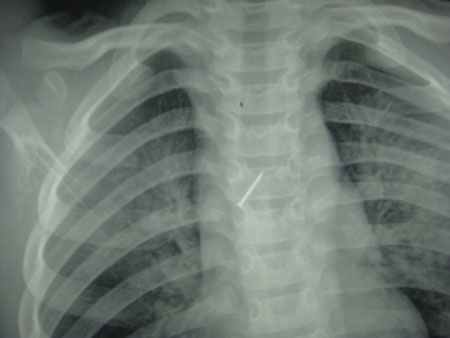

Chiếc đinh ghim trong phế quản bệnh nhi. Ảnh: BS cung cấp

Được chuyển đến bệnh viện Nhi T.Ư ngay trong đêm 25/4, bé được chỉ định chụp X – quang và xác định có dị vật ghim nằm sâu trong phế quản, đầu nhọn hướng về phía tim. Ngay lập tức, nhóm nội soi phế quản do Bs Lê Thanh Chương làm trưởng nhóm đã triển khai nội soi lấy dị vật cho cháu. Dị vật là một đinh ghim bằng sắt dài 2cm được lấy ra và tình trạng sức khỏe đã ổn định và đã được xuất viện.